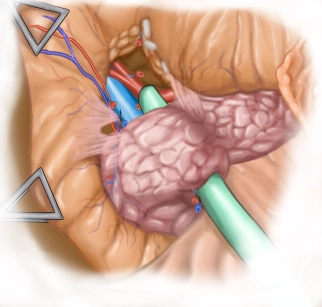

Iliakomesenterialer Venenbypass bei Verschluss der A. mesenterica superior